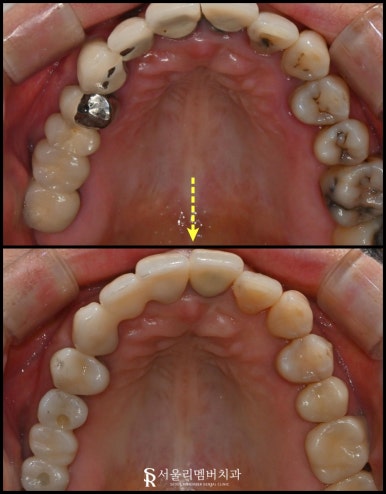

한쪽을 자세하게 보면

대합치가 빈 곳을 향해 정출된 것을 볼 수 있죠.

최종 보철

낙성대 치과 에 자체기공실에서

더 정확하고 고품질의 크라운을 제작해 드리는데요.

전후로 한번 보실까요?

이렇게 규칙이 잡혀있는 구강을 볼 수 있습니다.

마지막으로 전체적인 체크를 다시 해주고

접착 후 진료 마무리했습니다.